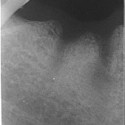

Foto 3: Radiografia dell’impianto

Foto 6: Il sorriso finaleIl paziente portava da diversi anni una corona in porcellana sorretta da un perno posto all’interno del canale della radice del 22 (incisivo laterale superiore sinistro).

Un processo carioso a carico della radice non permetteva la stabilità della corona e del suo perno (la corona in porcellana si staccava continuamente).

In questo caso la terapia d’elezione era l’estrazione della radice e l’inserimento di un impianto endosseo. Si è potuto procedere con la tecnica immediata e flapless cioè, estratta la radice viene inserito l’impianto senza tagliare la gengiva per sollevare il lembo di tessuto gengivale.

Tale tecnica, spesse volte, non è aplicabile perché, in mancanza di osso intorno alla radice, occorre rigenerarlo per inserire successivamente l’impianto.